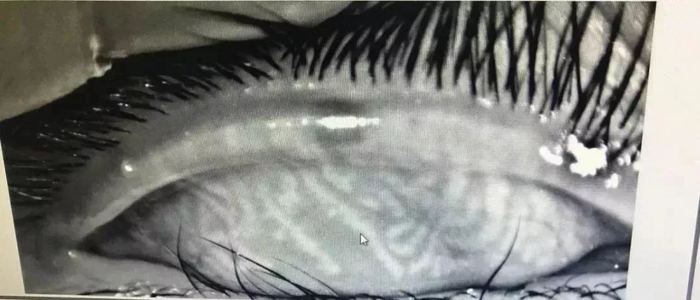

小辛的睑板腺检查图

正常人的眼睑上大约有32个睑板腺,平行竖线状排列,分泌油脂用来湿润眼球,而小辛的睑板腺已经“扭曲”成网状,模糊不清,相当于中老年人水平,甚至比有些中老年更差,所以眼睛会感觉到刺痛、灼烧感进而睁不开,并且小辛的睑板腺功能彻底恢复是不可能的,只能靠治疗来缓解症状了。